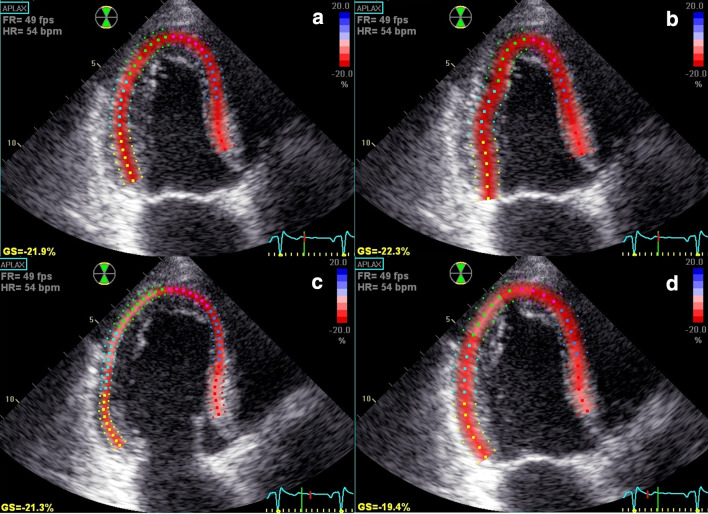

ROI was carefully placed at the level of the mitral cusp insertion while the aortic root was avoided. The inner layer was placed along the identification of the LV endocardium, as applied in LV volume measurements by the Simpson’s rule, cutting through papillary muscles and with inclusion of the apical endocardium. In order to avoid bias, the reference value by manually adjusted approach was measured before assessing the default semi-automated GLS value. Consecutive measurements were then made with different ROI widths, wide, medium and narrow for all three apical views. The different varieties of GLS measurements according to the ROI in this study are exemplified in the long axis views in a patient treated for NSTEMI (Fig. 1).

Fig. 1.

The impact of different ROI adjustments on the GLS values from the apical long chamber view in a 75 years old male with NSTEMI. a Manually adjusted expert GLS with ROI level medium selected for the reference value by the expert. GLS = − 21.9%. b Default GLS presented with selected ROI level wide by the software. GLS = − 22.3%. c Manually adjusted GLS with fixed ROI level narrow. GLS = − 21.3%. d Manually adjusted GLS with fixed ROI level wide. GLS = 19.4%